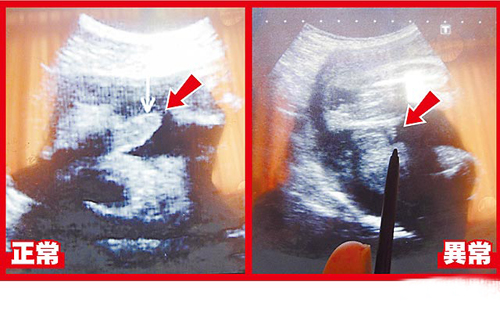

超聲波可看到胎兒生殖器,左圖箭頭處為28周正常男嬰生殖器:右圖箭頭處為異常男嬰28周時(shí)生殖器畫(huà)面。圖片來(lái)源:臺(tái)灣媒體

據(jù)報(bào)道,臺(tái)中大里仁愛(ài)醫(yī)院婦產(chǎn)科醫(yī)師李瑞祺說(shuō),這名30歲產(chǎn)婦在懷孕28周時(shí)出現(xiàn)密集陣痛,醫(yī)院緊急幫她安胎、進(jìn)行超聲波等檢查,赫然發(fā)現(xiàn)胎兒生殖器特別短,陰囊還是空的,懷疑染色體或基因異常導(dǎo)致生殖器過(guò)短與隱睪癥。但孕婦在26周時(shí)曾進(jìn)行羊膜穿刺檢查,顯示性染色體正常。